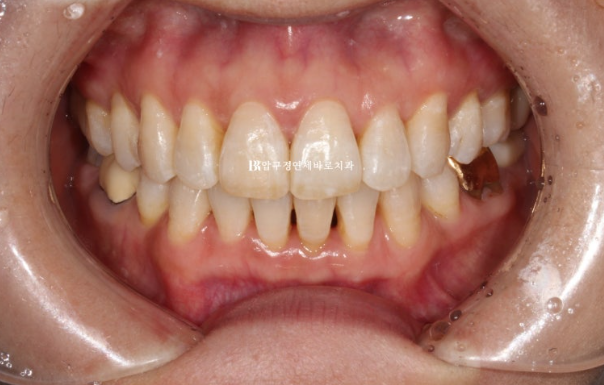

24.05

위 앞니 블랙트라이앵글은 치간삭제를 통해 줄었으나 삐뚤했던 아래 앞니가 가지런해지면서 블랙트라이앵글이 생겼습니다.

아래도 마찬가지로 치간삭제를 통해 블랙트라이앵글 사이즈를 줄였지만 치간삭제는 치아에 무리가지 않는 선에서 하는 것이 좋습니다.

걱정하시는 교합도 좋습니다.